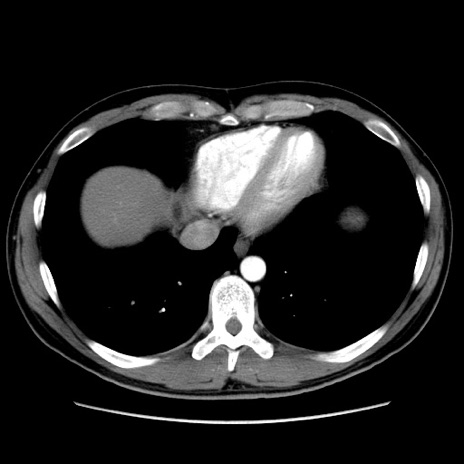

症例36(横断像)

【症例】20歳代 男性

【主訴】心窩部痛

【現病歴】今朝より上腹部痛あり。一旦軽快していたが再度出現したため救急要請。昨日夕に白身の魚を含む刺身を食べた。

【身体所見】BP 136/89mmHg、HR 74/min、BT 37.0℃、腹部:膨満、軟、心窩部に圧痛あり。反跳痛なし、筋性防御なし、腸雑音やや亢進あり。

【データ】WBC 17700、CRP 0.48